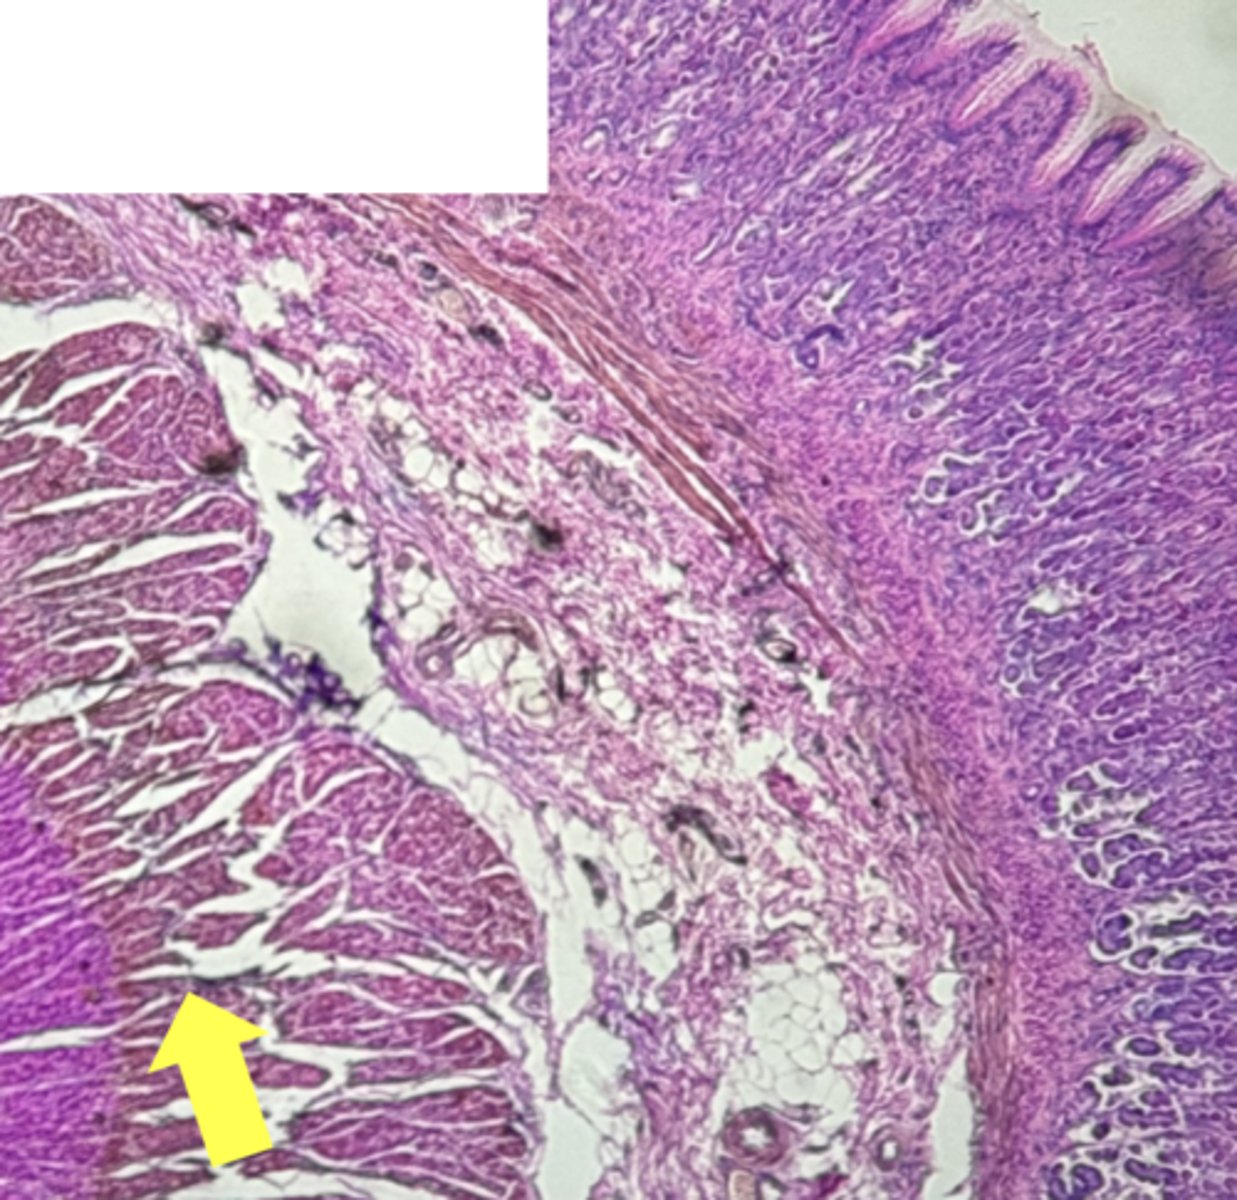

A- Esophagus

B- Stomach

Name the Tissue A & B

stomach

name the tissue

mucosa

(stomach)

submucosa

muscularis externa (3 LAYERS-KEY CHARACTERISTIC)

oblique layer

circular layer

longitudinal layer

simple columnar epithelium

gastric pits (KEY CHARACTERISTIC)

gastric glands (KEY CHARACTERISTIC)

Parietal cells- HCl (hydrochloric acid)

name the cell & what it secretes

Chief Cells- pepsinogen/pepsin

Lamina propria

muscularis mucosae

Esophagus

(esophagus)

muscularis externa

stratified squamous epithilium (KEY CHARACTERISTIC)